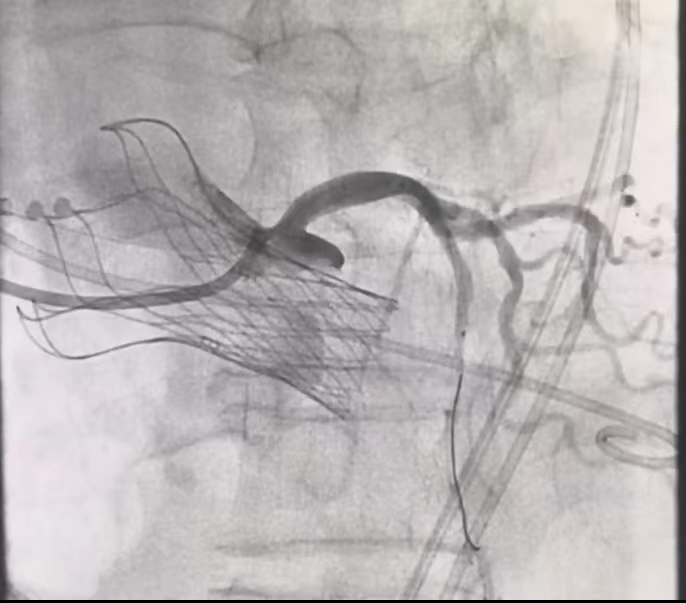

5,开窗支架释放后造影